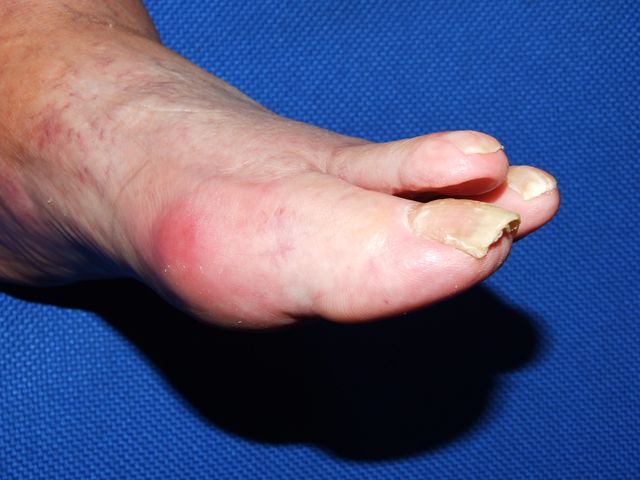

Bursitis primer metatarsiano